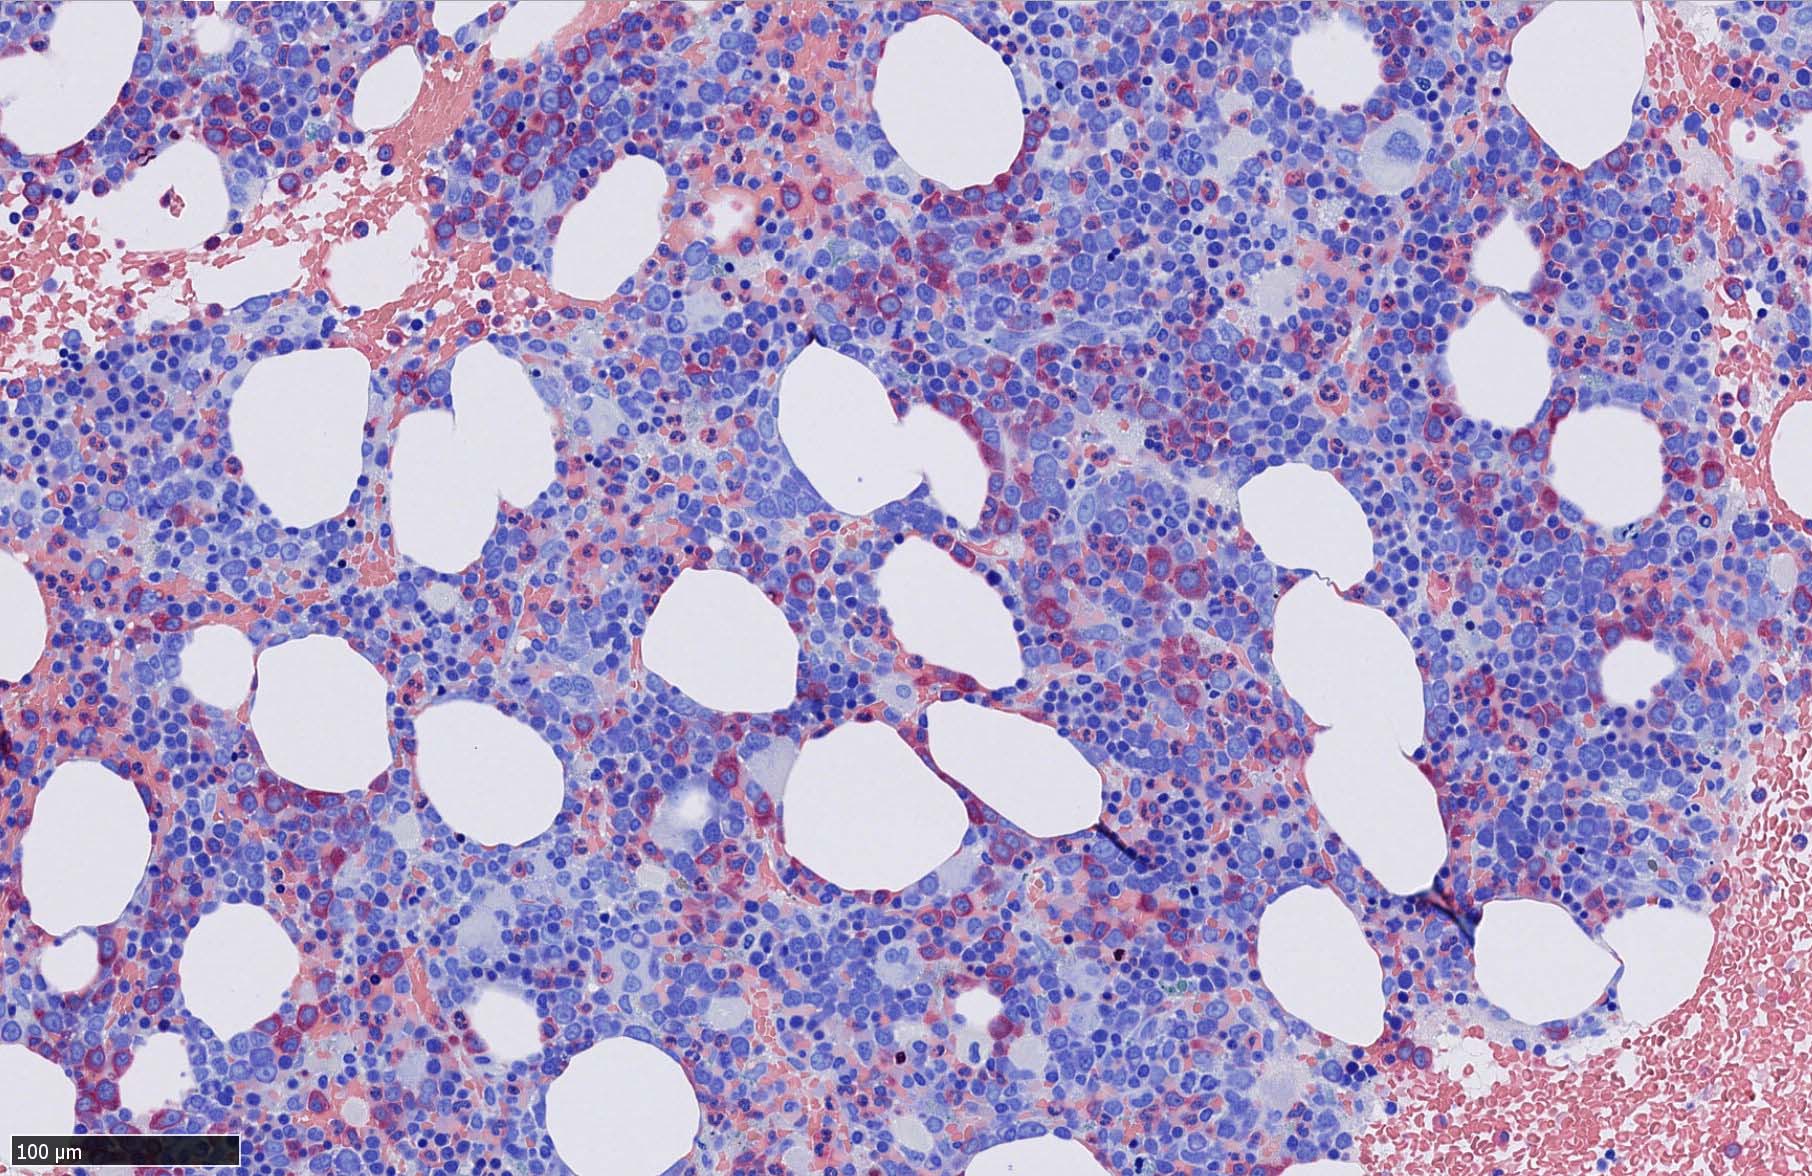

組織, 細胞病理

症例  画像サムネイルはクリックして大きな画像が見られます.

皮膚病変

blasticという名前から「大型細胞」を想起するが, この症例のようなclassical typeの細胞は思ったほど大きくはない. CD123陰性リンパ球とくらべてもあまり大きくないことがわかる.(散在する大型細胞はlysozyme+)

形態は均一で多型はめだたない.

免疫染色

腫瘍細胞は真皮を主座として, 皮下脂肪織まで, びまん性かつ単調monotonousに増殖することが多く, 表皮向性はみられない. 本例では血管や付属器中心あるいは脂肪織内に結節状の浸潤増殖を示した.

本例皮膚真皮増殖細胞はCD4+, CD56+, CD123+, CD303+, lysozyme(-). がん研有明病院, Sakamoto K, Takeuchi K先生にconsultationを行い, TCF4, TCL1の陽性が確認された.(consultationを受けていただいた両先生に深謝いたします.)